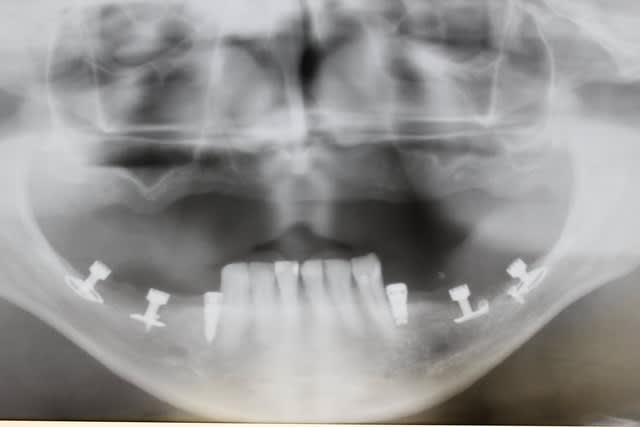

Le dentascan de la mandibule pour que vous compreniez mieux la difficulté...quais impossible de la considérer en cylindres même en déplaçant le NDI vous n avez aucune hauteur exploitable... Même des lame de Likow n y passent pas et les sous périostés sont interdits en Europe

J ai perdu mes deux foutus cylindres et ai dû les remplacer par deux double disk...et changer les deux mono disk du secteur droit

Et oui l implanto basale n est pas non plus un long fleuve tranquille